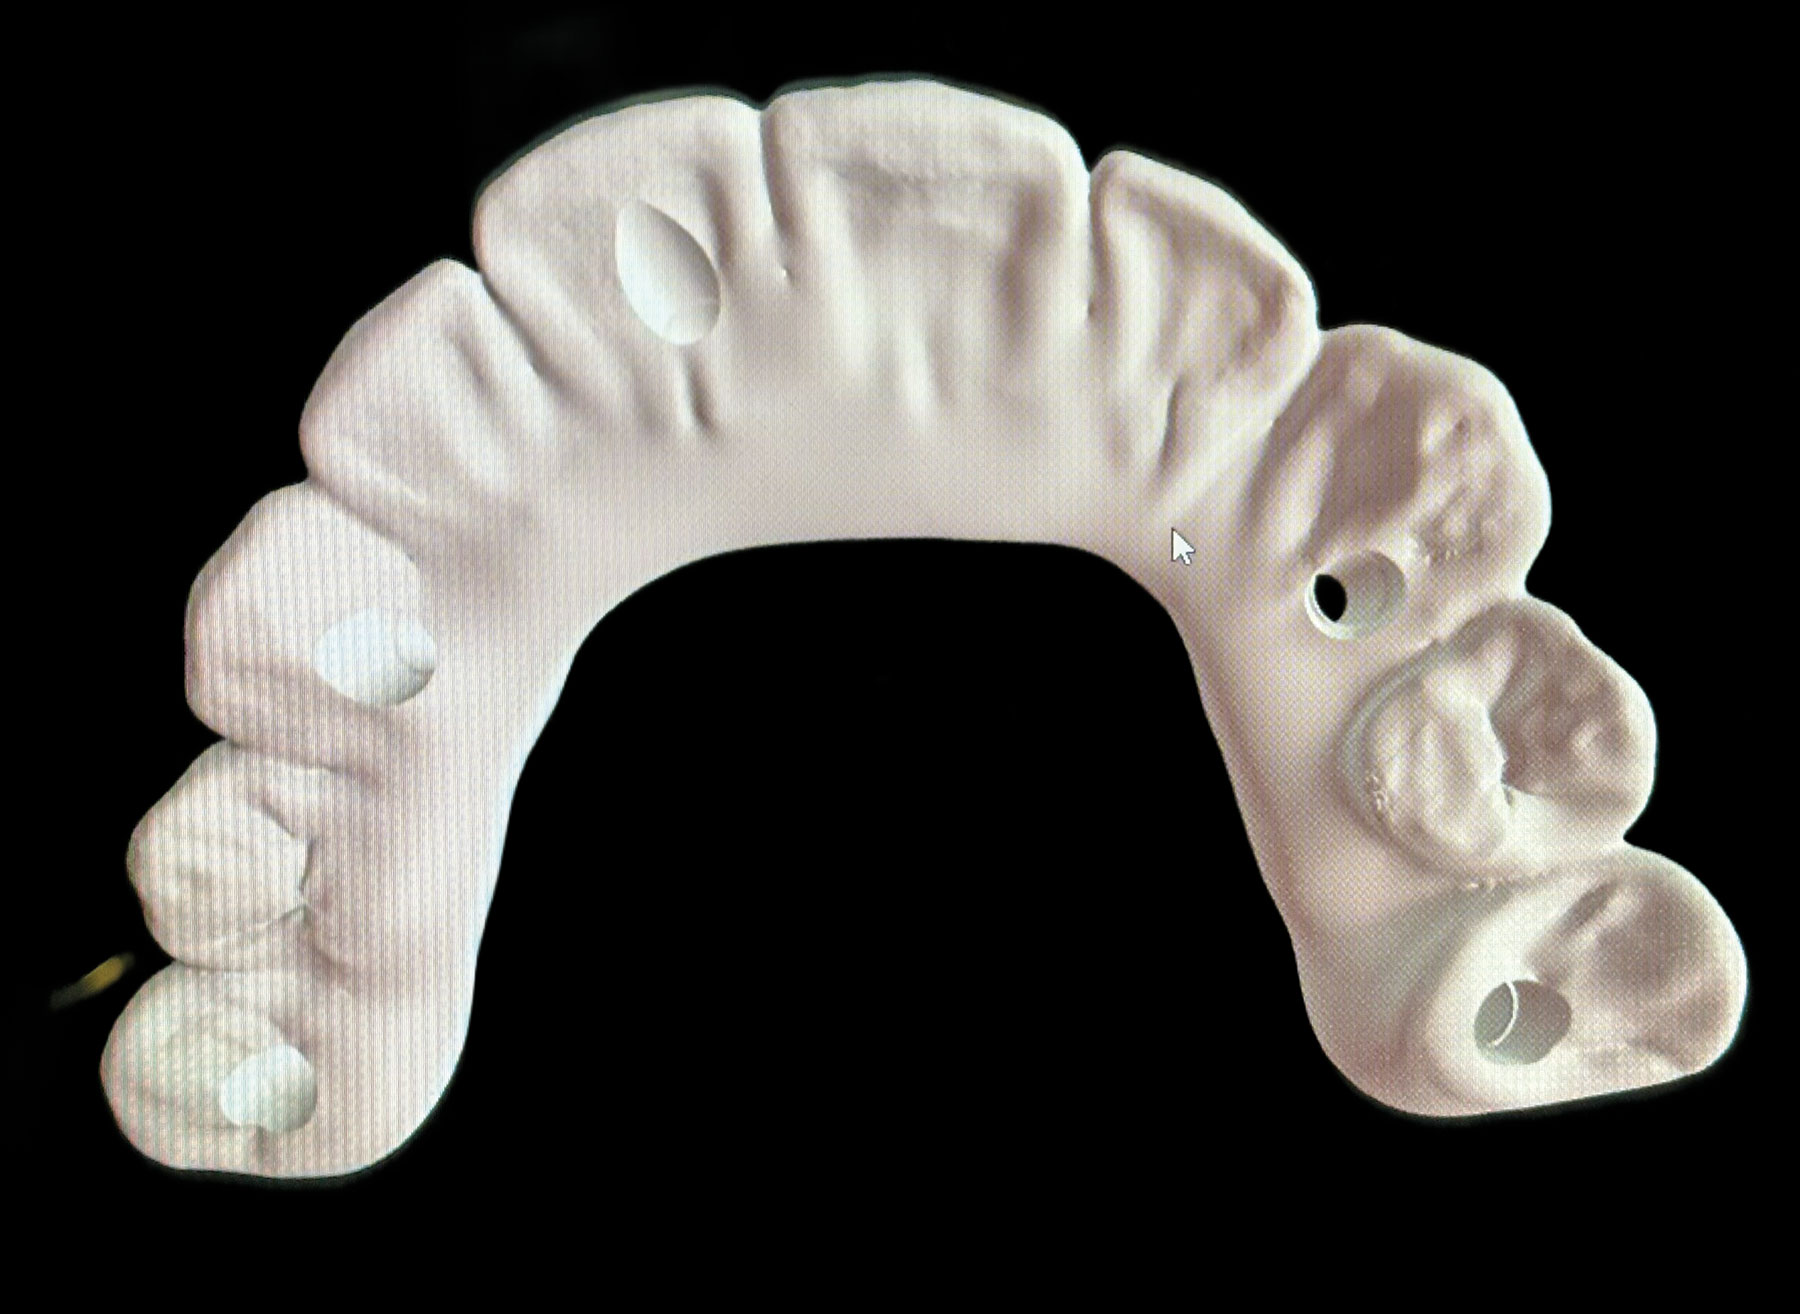

Fig 31. Mandibular provisional prosthesis printed demonstrating screw-access holes in prosthetically correct positions.

Figure 31